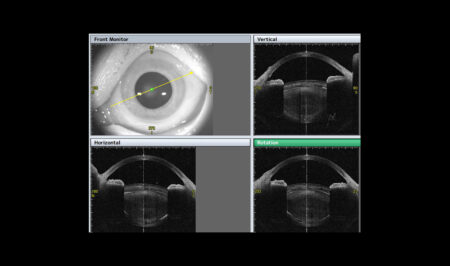

- topografia rogówki, dobór soczewek wewnątrzgałkowych i ich kalkulacja,

- analiza kształtu soczewki,

- Symulacja fakijnej soczewki wewnątrzgałkowej